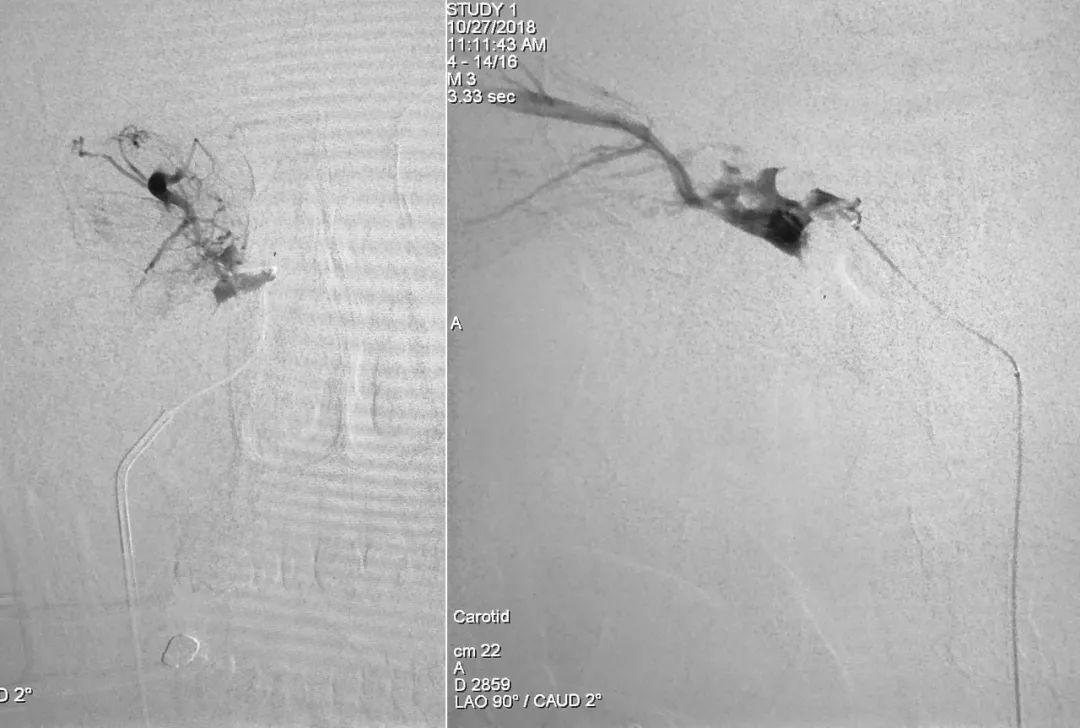

⑧ 术后左侧颈总动脉造影显示瘘口不显影:

将造影管移入右侧颈总动脉,正、侧位造影显示瘘口不显影:

正、侧位蒙片显示Onyx-18胶在右侧海绵窦内的铸型(约4.5 mm):